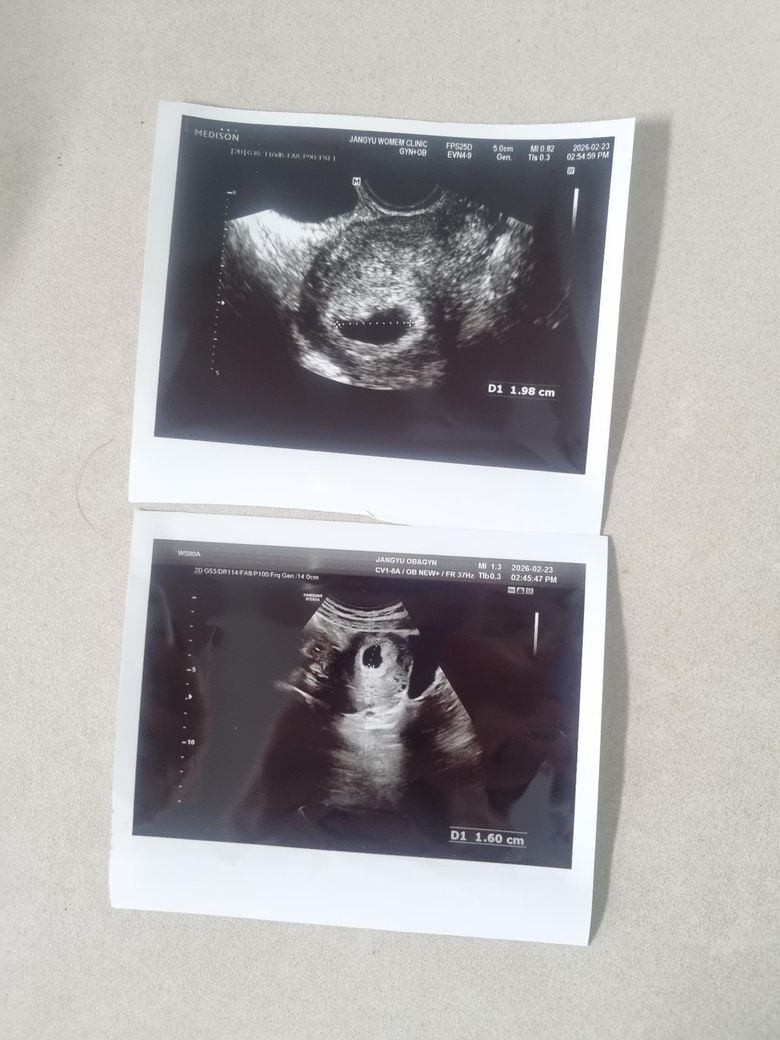

5주차 4일쯤인데 아기집 크기가 1.98cm가 나왔어요.

지금 난황이 안보이는데.... 유산될까봐 두렵습니다. 찾아보면 5주차에 아기집이 1.98센치나 되는 경우를 거의 못보는데.

사진상 난황이 없는게 맞겠죵...?

• 1번 째 사진

말씀하신 1.98 cm는 19.8 mm에 해당합니다. 이 수치가 평균보다 커 보일 수는 있으나, 단일 측정값만으로 비정상으로 단정하기는 어렵습니다. 특히 초음파상 임신낭 내부에 난황(yolk sac)이나 태아심박이 아직 보이지 않는 경우라도, MSD가 25 mm 이상이면서 태아가 보이지 않을 때를 비정상 임신(무배아 임신, anembryonic pregnancy)으로 진단하는 것이 일반적인 기준입니다. 이는 ACOG 및 RCOG 가이드라인에서도 비교적 엄격히 적용하도록 권고하고 있습니다. 따라서 19.8 mm에서 난황이 보이지 않는다는 사실만으로 유산을 진단하지는 않습니다.

사진상으로는 중심부의 저에코성 구조가 임신낭으로 보이며, 작은 고에코성 원형 구조가 명확히 구분되지는 않습니다. 다만 사진 한 장으로 난황 유무를 확정하기는 어렵고, 실제 판독은 실시간 질식 초음파 영상과 임상 정보가 함께 고려되어야 합니다.